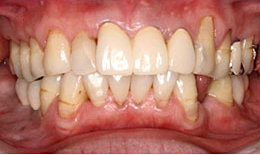

治療後

下顎

保存困難な歯を抜歯後、インプラントを4本埋め込んで、セラミックスクラウンを被せた